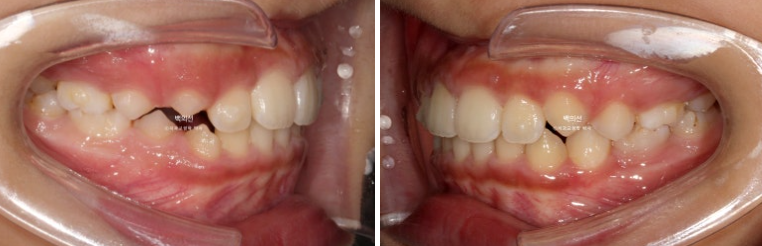

9개월 후 모습을 보면 송곳니와 작은어금니들이 많이 올라온 게 보입니다.

24.11

이제 슬슬 재제작을 할 타이밍입니다.

2024년 11월에 재제작을 시작, 24년 12월부터 재제작한 장치를 끼기 시작했습니다.